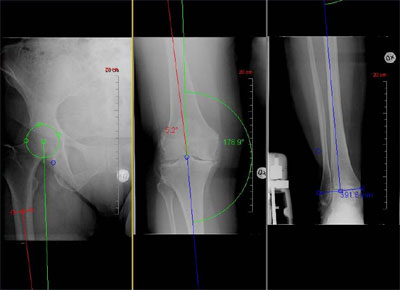

整形外科診療に特化した計測イメージ(左から、大腿、膝、足首)

そこで,今回販売を開始する「OrthoPlanner Pro」では,骨折治療・人工関節手術のプランニングを画面上でデジタルに実施でき,かつX線撮影による患部データの拡大率の誤差を補正する機能※を実現した。

また,国内のユーザ(整形外科医)が本ツールを使用する際の作業効率の向上を念頭におき,国内外の主要インプラントメーカ13 社の人工関節テンプレートをデジタルテンプレートとして実装するとともに,プランニングにおける標準的な計測・作図方法をクリックのみで行えるようにするなどの機能を実現した。

- 整形外科医が求める様々な機能をワンクリックで実現する整形外科計測・作図ツール